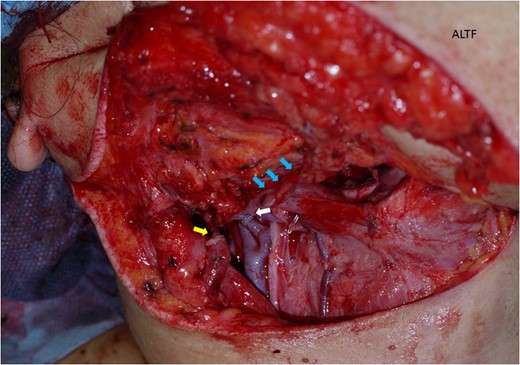

A free antero-lateral thigh flap was harvested from her right thigh.

The antero-lateral thigh flap (ALTF) was transferred to her neck area. The descending branch of lateral circumflex femoral artery (blue arrows indicating) was anastomosed her right facial artery. A comitant vein was anastomosed to her external jugular vein in end-to-end fashion with a 2.5 mm microvascular anastomotic device (yellow arrow). The other comitant vein was anastomosed in the same way to a branch of internal jugular vein (white arrow).